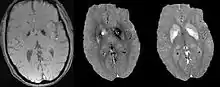

Morphology enabled dipole inversion (MEDI)

A unique advantage of MRI is that it provides not only the phase image but also the magnitude image. In principle, the contrast change, or equivalently the edge, on a magnitude image arises from the underlying change of tissue type, which is the same cause for the change of susceptibility. This observation is translated into mathematics in MEDI,[13] where edges in a QSM which do not exist in the corresponding magnitude image are sparsified by solving a weighted norm minimization problem.[14]

MEDI has also been validated extensively in phantom, in vitro and ex vivo experiments. In an in vivo human brain, MEDI calculated QSM showed similar results compared to COSMOS without statistically significant difference.[15] MEDI only requires a single angle acquisition, so it is a more practical solution to QSM.